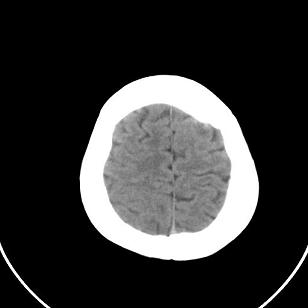

双侧脑室边缘呈波浪样,没有见过?

只有一层显示双侧侧脑室边缘不规则,呈波浪状,不排除部分容积效应,我做的话薄层再扫描一下

正常,侧脑室纵络丛走行血管

正常,考虑侧脑室脉络丛走行血管